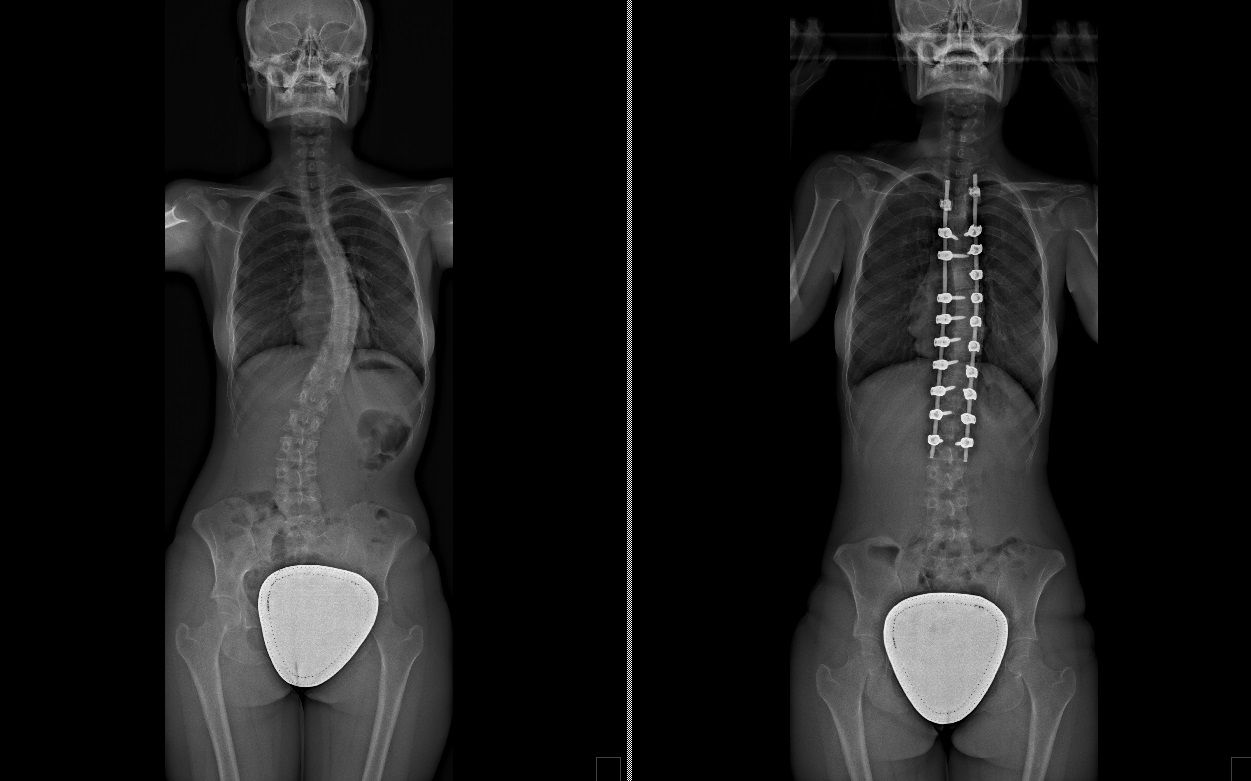

Laureato in Medicina e Chirurgia presso l'Università degli Studi di Napoli Federico II nel 2011, Specializzato in Ortopedia e Traumatologia presso la stessa Università nel 2017. Da subito ho dedicato i miei studi all'ambito della chirurgia vertebrale e della neurochirurgia. Infatti ho frequentato per 9 mesi tra il 2015 ed il 2016 i reparti di Neurochirurgia dell'IRCCS Neuromed di Pozzilli (IS) per apprendere le tecniche di trattamento delle Patologie della Colonna Vertebrale. Da allora il mio principale interesse è rivolto al trattamento conservativo e, dove necessario, chirurgico delle deformità della colonna vertebrale, sia dell’età dell’accrescimento che degenerative dell’adulto: scoliosi, dorso curvo, spondilolisi, spondilolistesi. Ulteriori campi di interesse sono il trattamento di lombalgia e lombosciatalgia, ernia del disco, stenosi del canale vertebrale, fratture vertebrali traumatiche o da osteoporosi (vertebroplastica), terapia del dolore osteoarticolare mediante tecniche mininvasive (radiofrequenze). Dal 2017 sono Consulente presso IRCCS Neuromed di Pozzilli (IS) con incarico di Responsabile del Centro per la Diagnosi e Cura delle Deformità Vertebrali e Scoliosi, dove svolgo la mia attività chirurgica in regime di convenzione. Svolgo la mia attività chirurgica in regime di solvenza e di convenzione assicurati presso la Clinica Ruesch di Napoli. Continuo costantemente la mia formazione con esperienze di perfezionamento nazionali ed internazionali. Infine, dal 2020 sono Docente per l'Università degli Studi di Roma "La Sapienza".

Foto e video